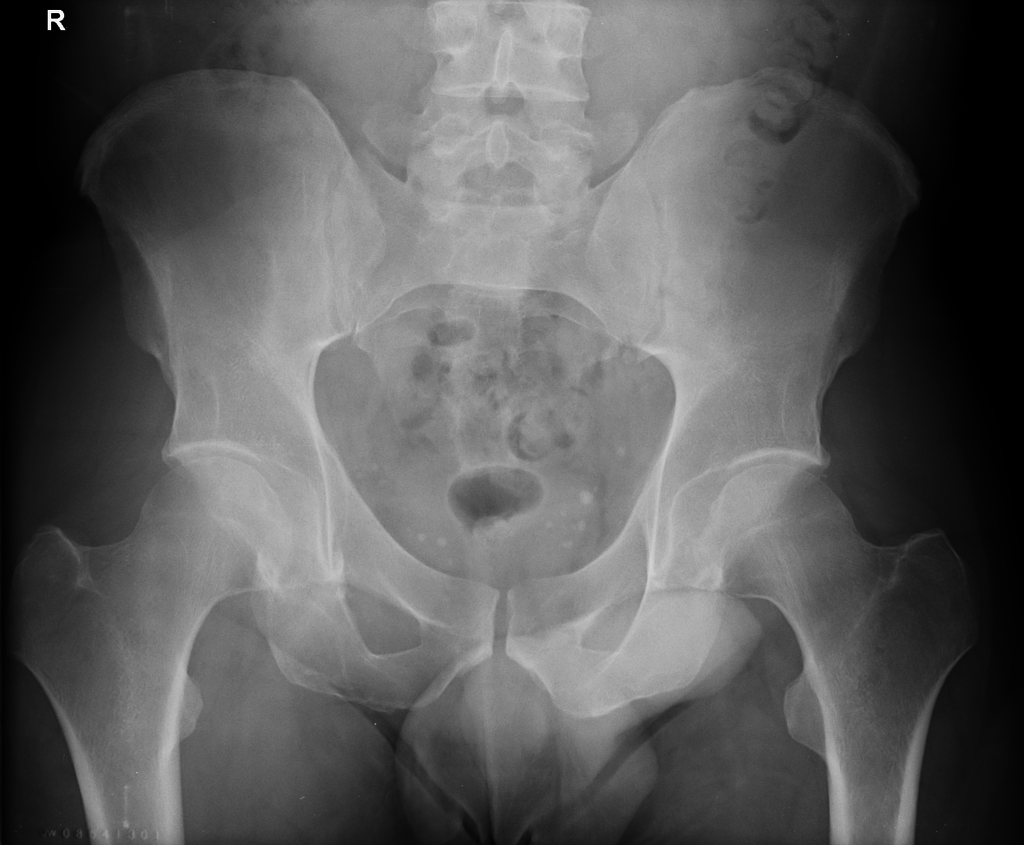

Hip effusion

Left sided effusion due to occult acetabular fracture

Source: Radiopaedia

While radiographic diagnosis of hip joint effusion is as non-specific as any other radiographic effusion diagnosis, aetiology can sometimes be determined by the clinical context. More common causes in adults are septic or inflammatory arthropathy.